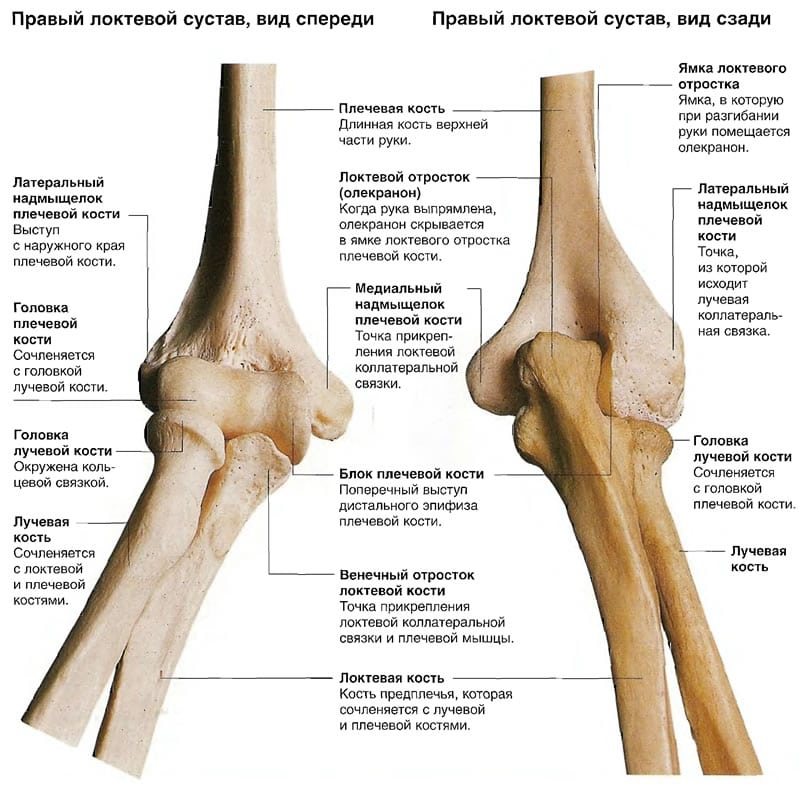

Локтевой сустав состоит из трех костей, общей суставной капсулы, связок и сухожилий. Последние представляют собой продолжения мышц предплечья, которые крепятся к надмыщелкам плечевой кости. Эти мышцы активно сокращаются при игре в теннис, занятиях боксом, игре на музыкальных инструментах и выполнении тяжелой работы. Все это приводит к перенапряжению и микротравматизации сухожилий.

В 80-90% случаев у человека поражаются сухожилия, которые крепятся к латеральному (наружному) надмыщелку. Их регулярная травматизация приводит к микроразрывам и дальнейшему развитию воспалительного процесса, который нередко распространяется на надкостницу. У человека появляются боли и чувство скованности в локте, мешающие ему заниматься привычной деятельностью.

Воспаление в области наружного надмыщелка плечевой кости называют латеральным эпикондилитом или локтем теннисиста. Именно об этом заболевании и пойдет речь.